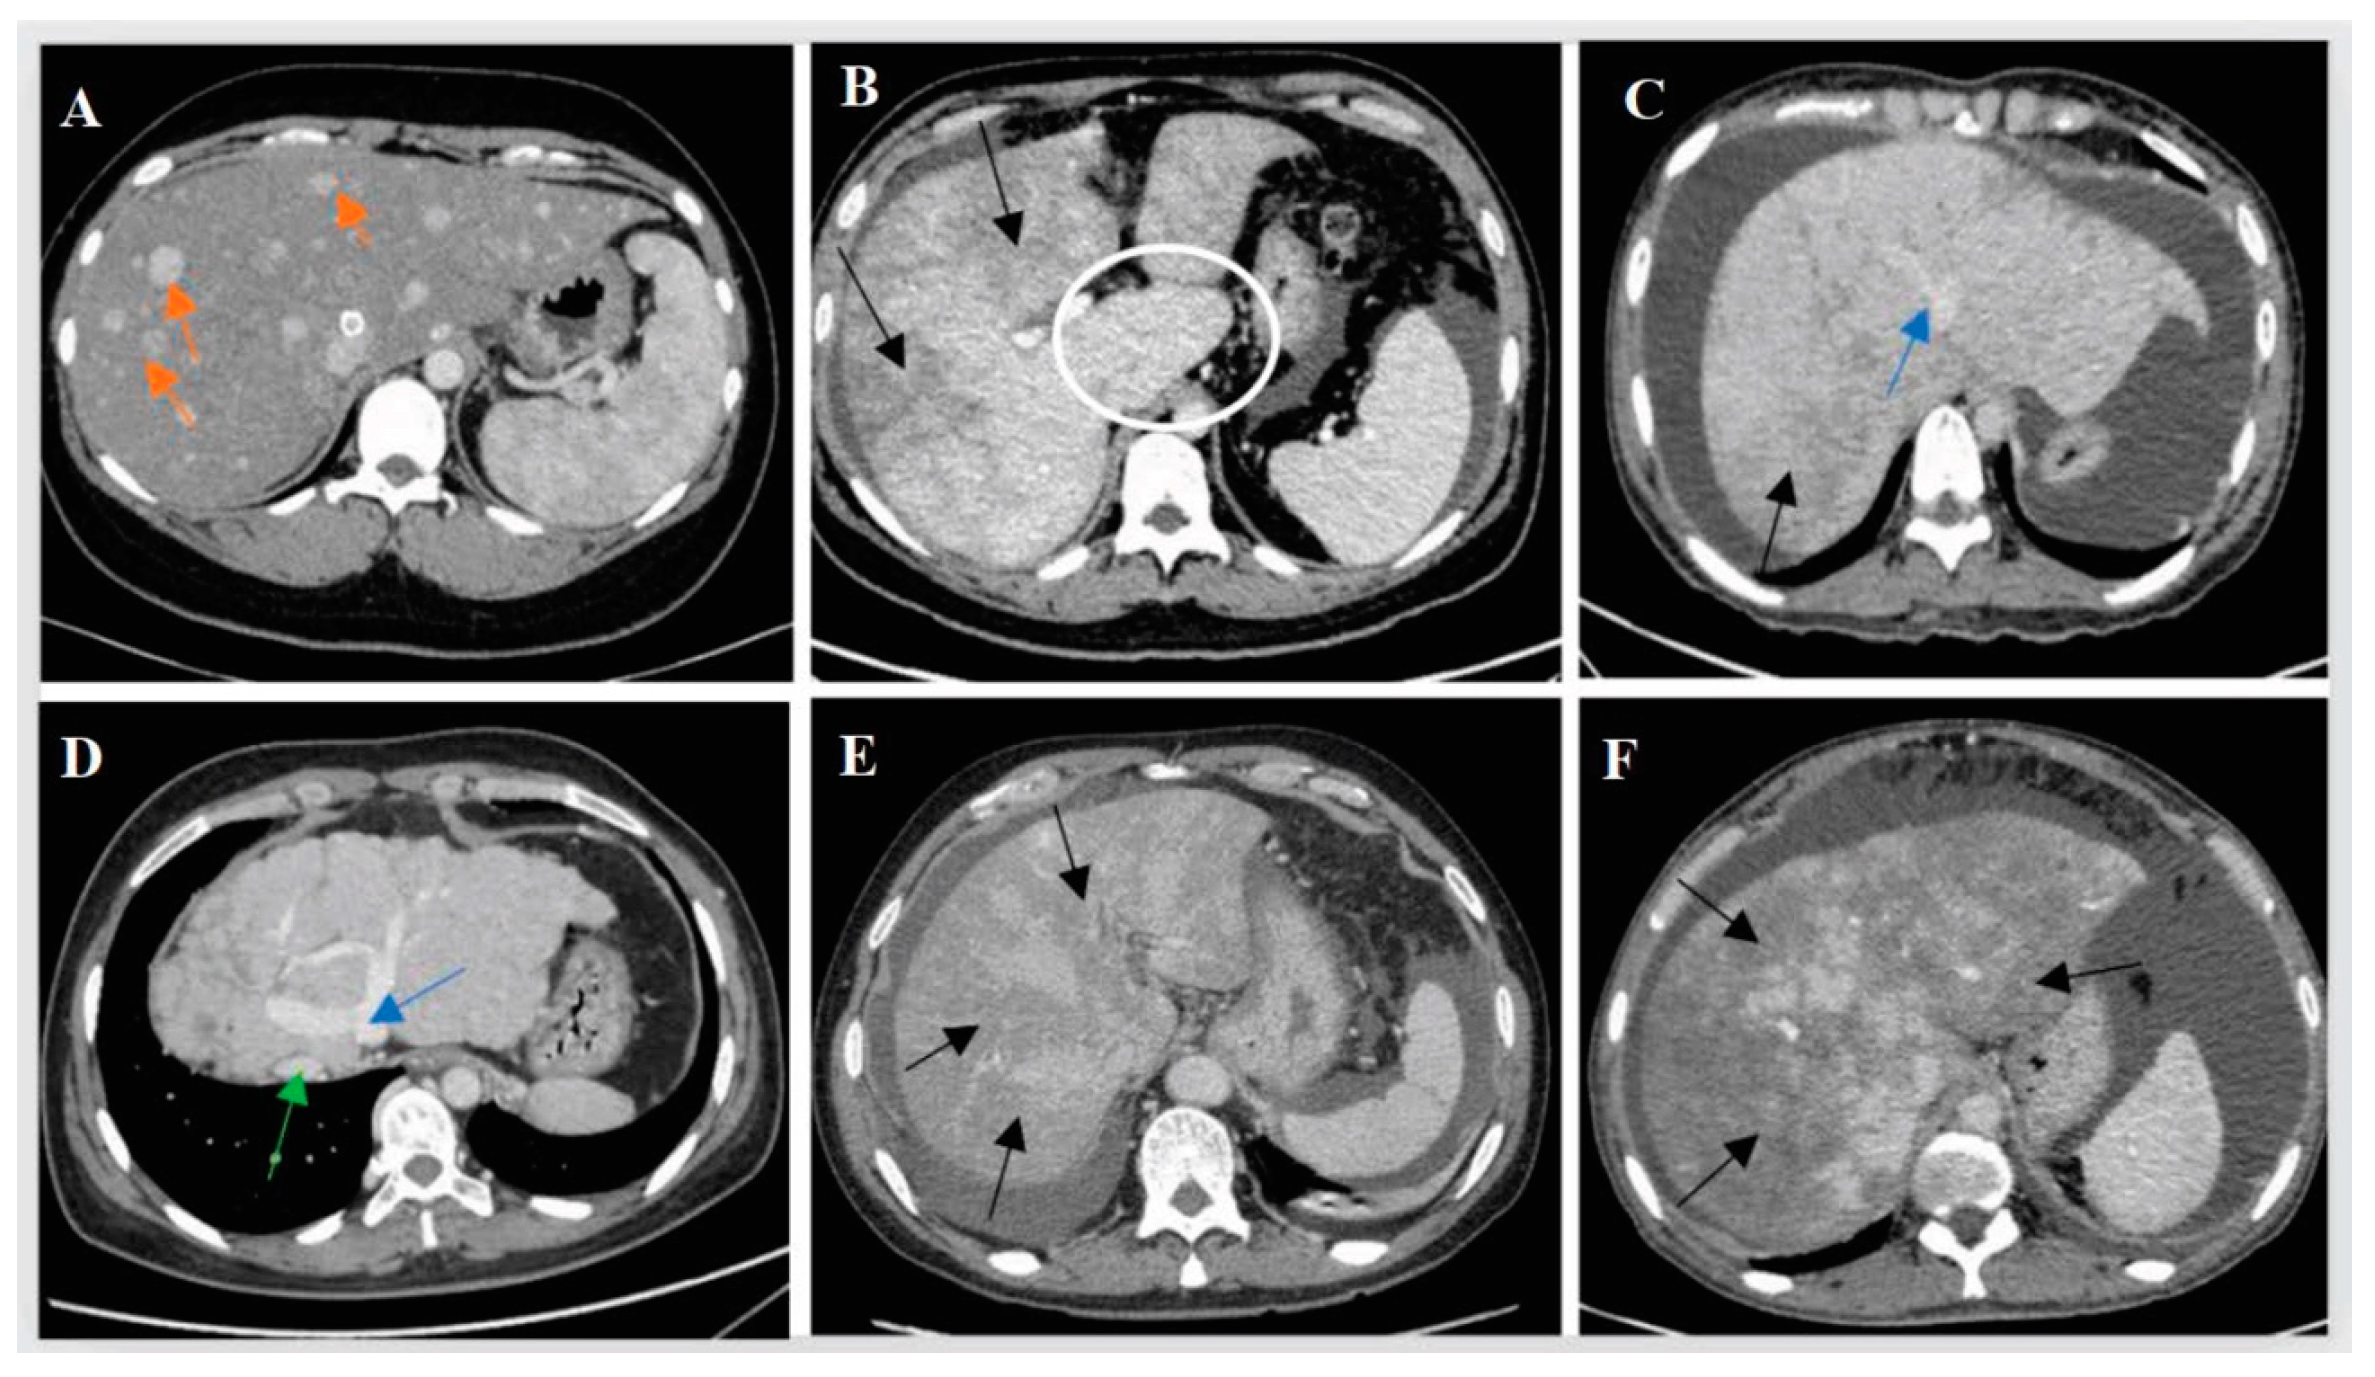

3.3. Imaging Findings

| Portal vein thrombosis, % (n/N) | 4.4% (6/136) | 11.70%(30/257) | 0.018 |

| Localized stenosis or occlusion of the hepatic veins, % (n/N) | 100.00% (130/130) | 1.20% (3/256) | <0.001 |

| Imaging manifestations of cirrhosis, % (n/N) | 47.10% (65/138) | 2.00% (5/256) | <0.001 |

| Hepatomegaly, % (n/N) | 56.20% (73/130) | 67.10% (163/243) | 0.037 |

| Splenomegaly, % (n/N) | 63.80% (78/130) | 16.10% (39/242) | <0.001 |

| Collateral circulation of hepatic veins, % (n/N) | 73.90% (99/134) | 0 | <0.001 |

| Patchy liver enhancement, % (n/N) | 78.46% (102/130) | 92.66% (164/177) | <0.001 |

| Enlarged caudate lobe of the liver, n/N (%) | 47.70% (62/130) | 0 | <0.001 |

| Early strengthening nodules in the liver, n/N (%) | 8.50% (11/129) | 0 | <0.001 |

| Narrowed inferior vena cava, n/N (%) | 55.20% (69/125) | 44.20% (80/177) | 0.087 |

| Esophageal varicose veins, n/N (%) | 64.00% (80/125) | 21.20% (38/179) | <0.001 |